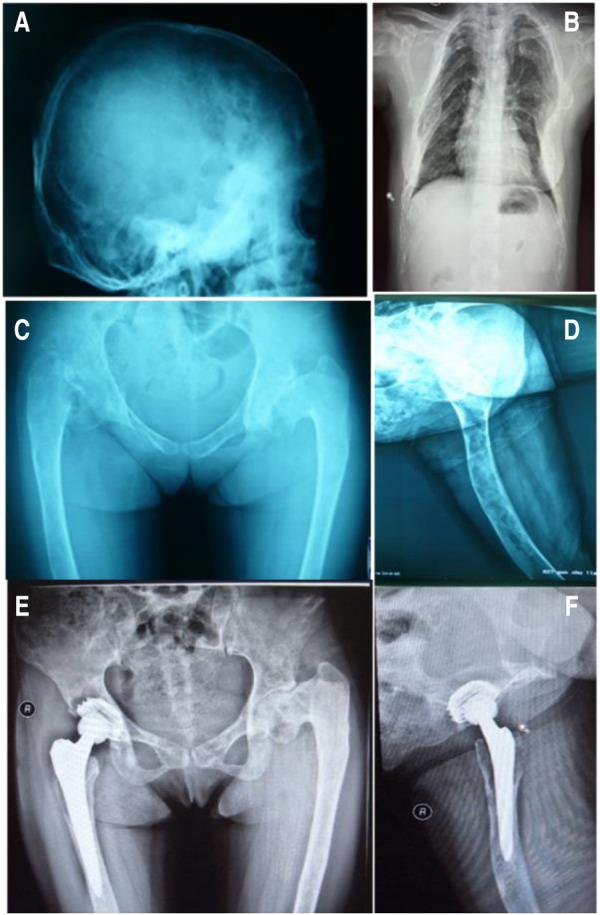

2009年12月,一名24岁的女性患者因“摔倒后右髋关节疼痛和活动受限1年”入院。该患者在一年多前摔倒后出现右髋关节疼痛,活动受限。休息后疼痛略有缓解,可以行走。根据提供的信息,患者有10年多发未经治疗的骨骼异常病史,包括双髋内翻畸形、屈曲挛缩、右髋内收畸形和双侧膝外翻畸形。入院时通过X光检查发现,下肢长骨和颅骨中存在多个骨致密影和磨玻璃影的囊性区域,骨皮质变薄,双侧股骨干和颈干角变形(图1)。此外,患者出生时有多处皮肤色素沉着,14岁时被诊断为面部骨骼畸形。患者月经正常,有第二性征,在24岁时自然分娩。

图1 首次入院时患者的X光片。ABCD:术前X线片,EF:右髋关节置换术后22个月

患者2009年至2013年间接受了四次静脉输注唑来膦酸5mg,同时口服补钙。2010年7月进行右侧全髋关节置换术(THA)。术后髋关节X线片见图1。碱性磷酸酶和骨钙素水平分别为538 IU/L和192.5 ng/ml。2013年12月,患者接受了矫形外科手术和右髁上截骨(图2)。入院时,碱性磷酸酶和骨钙素水平为403 IU/L和246.30 ng/ml。2015年5月,患者因跌倒导致左股骨干骨折,并接受了钢板和螺钉内固定(图3)。根据术后组织病理学,最终诊断为纤维发育不良。2015年12月,移除右侧股骨板,以防止应力集中和随后的股骨干骨折。尽管患者在随访期间没有出现明显并发症,但于2017年和2018年在另一家医院接受了颌下感染和下颌骨坏死的治疗(图4)。